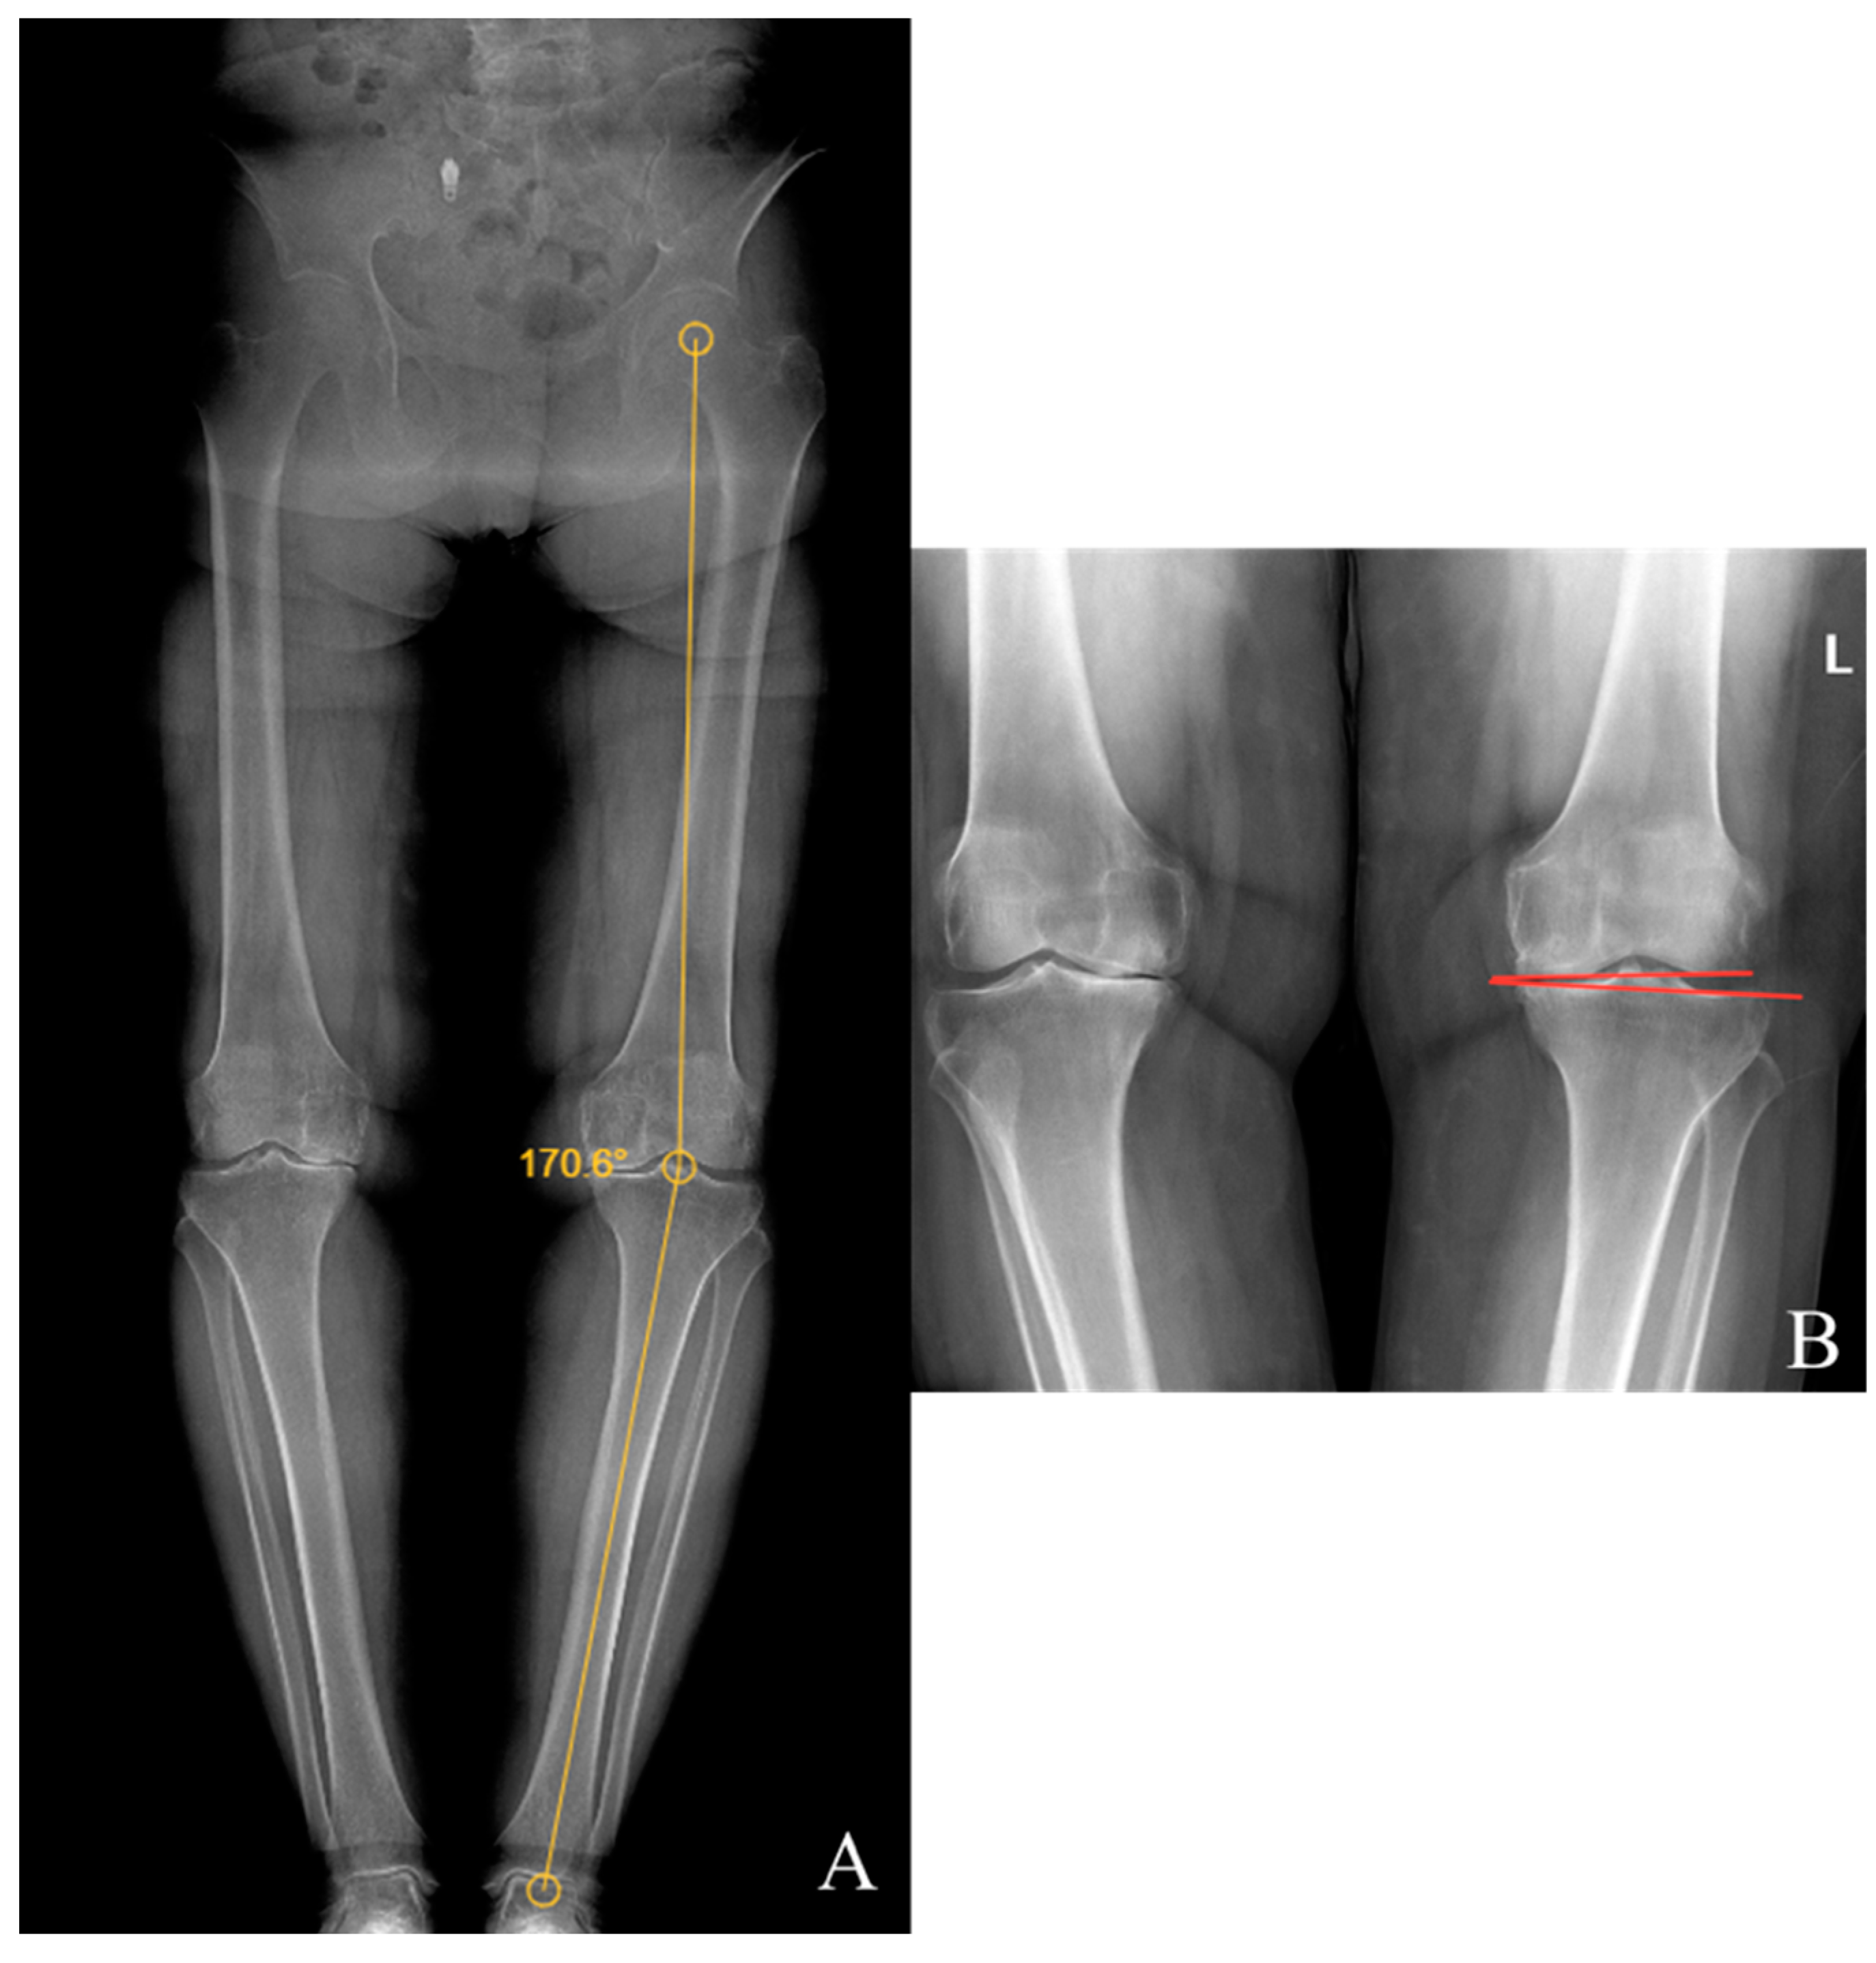

Preoperative and last visit full-leg standing radiographs were evaluated in each patient. Radiological measurements were performed using the picture archiving and communication system software. Two researchers independently measured the selected angles on all radiographs. The study utilized the average of the measured values. The hip–knee–ankle (HKA) angle was defined as the angle between a line drawn from the center of the femoral head to the femoral intercondylar notch and another line from the center of the tibial plateau to the mid-talar dome. The joint line convergence angle (JLCA) was measured as the angle between the femoral and tibial joint lines. The talar tilt (TT) angle was defined as the angle between the subchondral plate of the distal tibial articular surface and the talar dome, with the apex lateral angles positive and the apex medial angles negative. The ground talar dome (GT) angle was between the talar dome and a line parallel to the ground, and the ground plafond (GP) angle was between the subchondral plate of the distal tibial articular surface and a line parallel to the ground, both with apex lateral angles positive and apex medial angles negative.

The HKA, TT, JLCA, GT, and GP angles were measured on the patients’ radiographs (Figure 2 and Figure 3). The preoperative and last visit American Orthopaedic Foot & Ankle Society (AOFAS) scores were evaluated.

Figure 2. (A) Hip–knee–ankle angle; (B) knee joint line convergence angle.